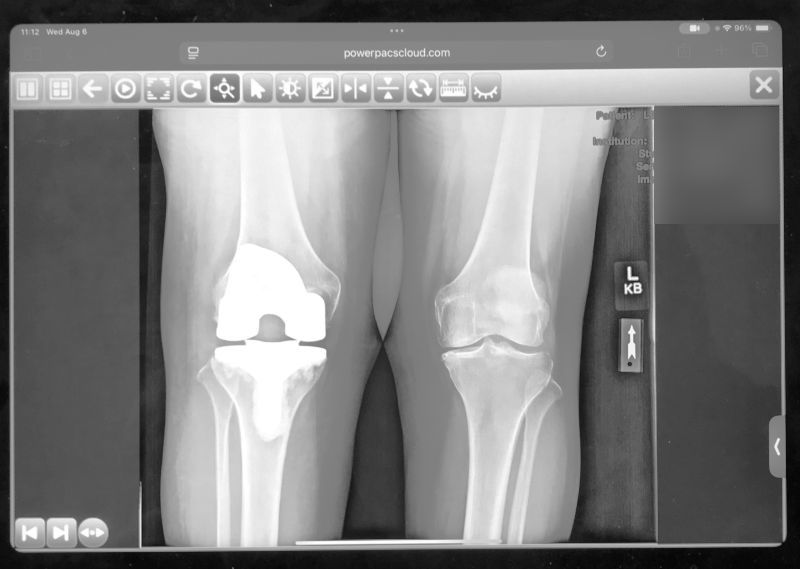

The one on the left is titanium and plastic.

(Three week checkup went very well.)

Deb's knee is doing great! Her lower back is a big problem. Painful. Ice, heat, vibration massage, advil, tylenol .... X-ray does not show any "damage" which is good.